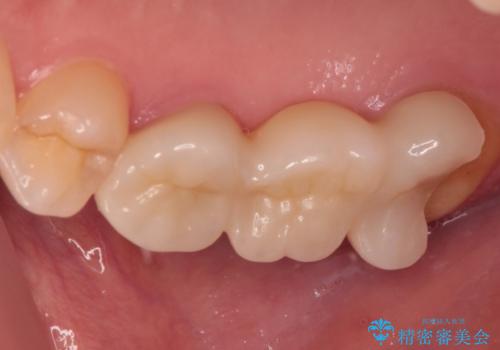

壊れやすいブリッジ インプラント治療で安定した咬み合わせに

- 頻繁に脱離を繰り返す奥歯のブリッジが欠けてしまったとのことで来院された患者様です。

外科処置を回避するためにブリッジ治療を選択されたそうですが、頻繁に脱離するので、欠けた部分のクラウンの作り替えと、欠損部のインプラント治療を行うこととしました。

最後方歯は、クラウンを維持するための高さが不足していたため、インプラント処置の際に歯冠長を延長する手術を併用し、維持力を増すこととしました。

上顎洞までの骨高さが低いケースでしたが、ショートインプラントと骨圧縮機能を持つドリルの使用により、上顎洞底挙上を行うことなく、インプラント治療を行うことができました。